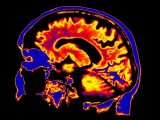

このネガティブ思考をワーキングメモリにこびりつかせることなく、なるべく早く取り除くにはどうすればよいのか。最新の研究では、fMRI(機能的磁気共鳴画像法)でモニターした脳活動のデータを分析することにより、ネガティブ思考を頭から取り除くための3つの最良の方法が明らかになっている。